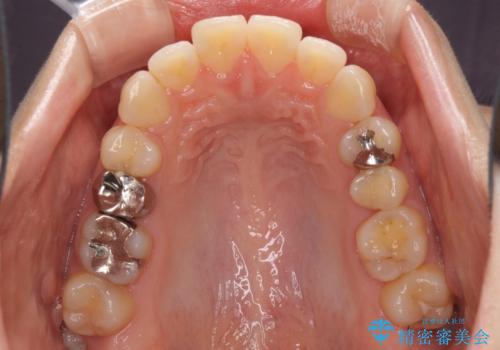

- 口元の閉じにくさと、前歯のでこぼこの歯並びを気にして来院された患者様です。

口元を積極的に引っ込めるために、上下左右の小臼歯計4本を抜歯することとしました。

セオリーでは第一小臼歯を抜歯しますが、上下右側は第二小臼歯に銀歯が装着されているため、第二小臼歯を抜歯することとしました。

上下正中を左右対称に揃えるため、アンカースクリューや補助装置を使用しながら口元を下げていくこととしました。